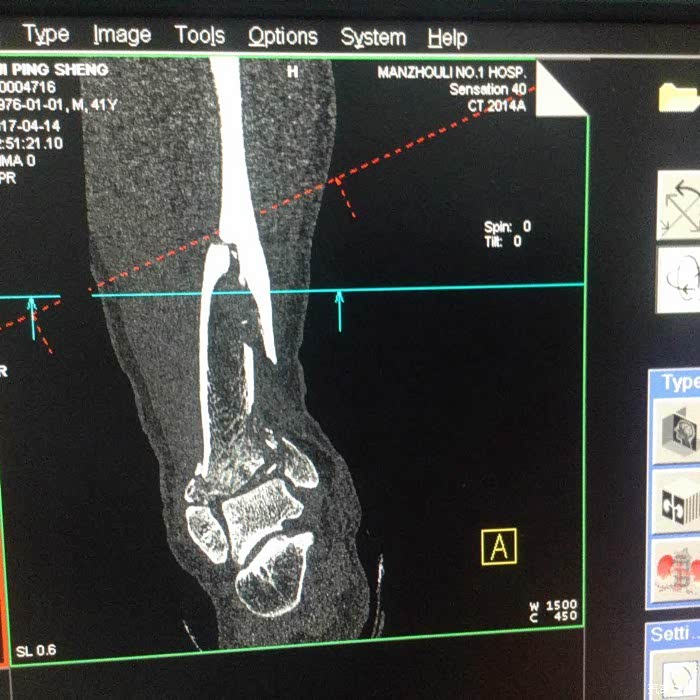

记得当时撞车后,我发现右脚像秤砣一样乱晃,我就明白了,厉害了我的哥。

此时还没有水肿,正在处理伤口看腿型大家可以看得出畸形了。

辗转反复,从广袤的呼伦贝尔满洲里市,层层找关系,来到了北京积水潭医院,终于住院,真是不容易,这是我第一次躺着坐飞机,躺着进北京。